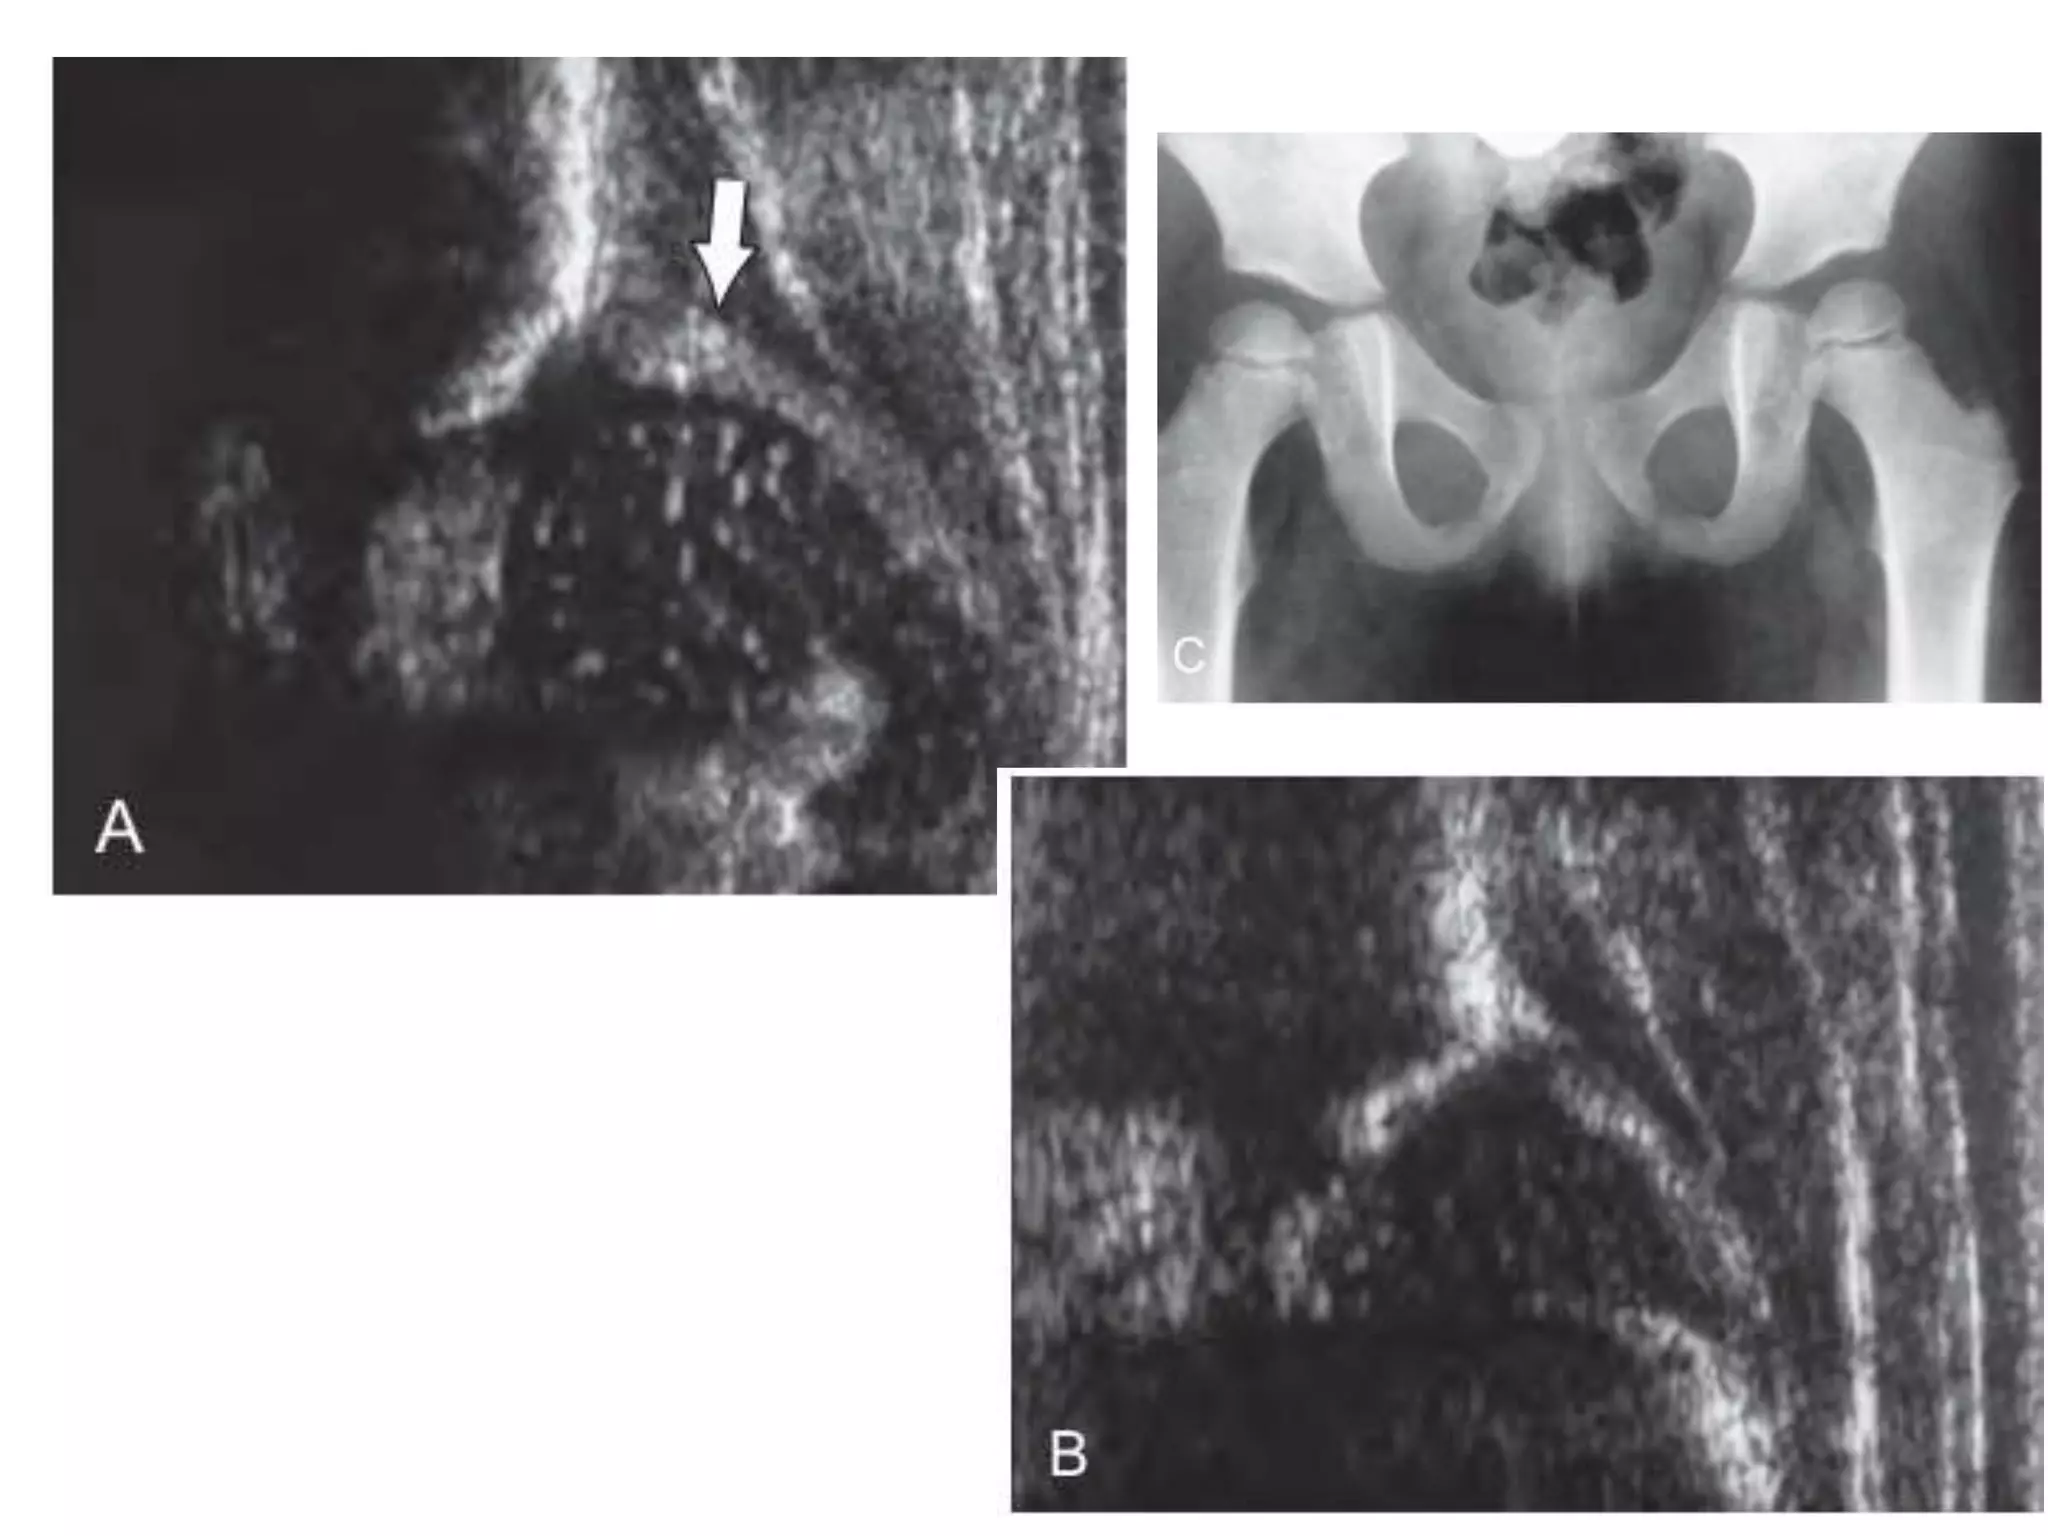

The pelvis of a 1-year-old boy shows a slightly

flattened acetabulum

1-year-old girl shows congenital

superolateral subluxation of the left hip

2-year-old boy demonstrates complete

superolateral dislocation of the right hip